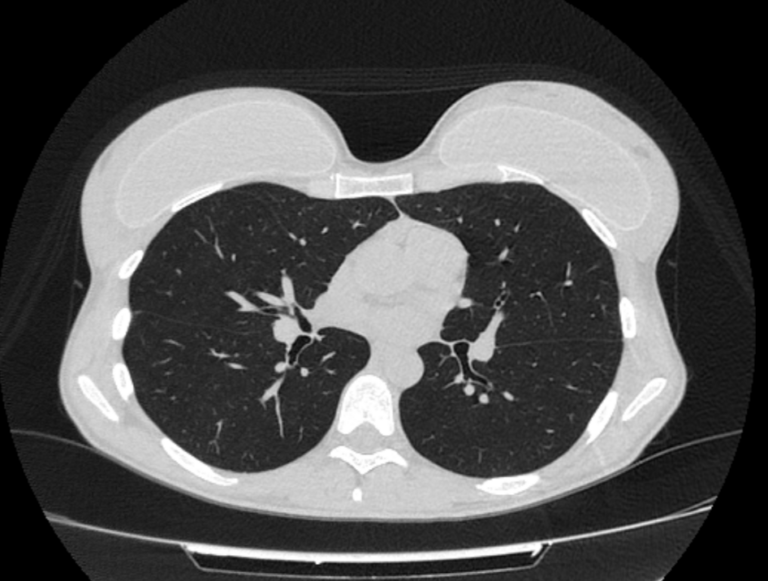

Во время исследования рентгеновская трубка томографа вращается вокруг исследуемой области и производит множество послойных снимков с шагом 0,5-1 мм. Полученные снимки поперечного сечения с помощью компьютерной программы могут быть преобразованы в 3D-изображения исследуемого органа или участка ткани. Это позволяет выявлять практически все заболевания легких на ранних стадиях и назначать своевременное лечение.

В медицинском центре «Доступная медицина» используется современный 128-срезовый компьютерный томограф TOSHIBA AQUILION CXL, на котором проводится сканирование легочной ткани. За счет увеличенного количества детекторов аппарат производит снимки с большой скоростью и минимальной дозой облучения. При этом инновационные цифровые приложения позволяют получить объемные изображения легочной ткани высокой четкости, контрастности и в мельчайших подробностях.